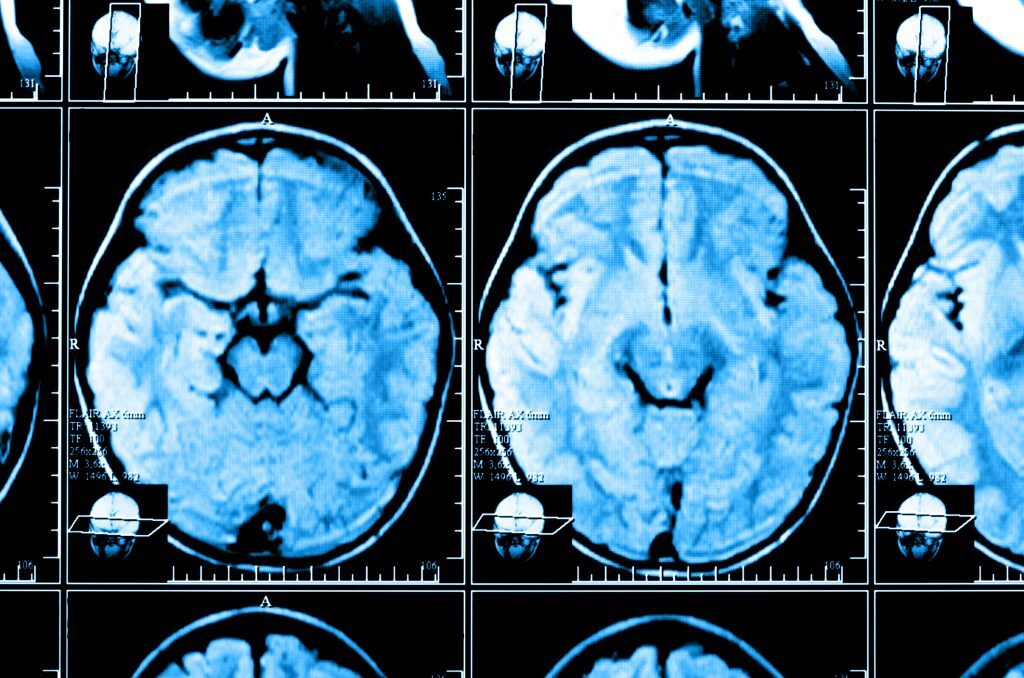

X-ray image of the brain computed tomography